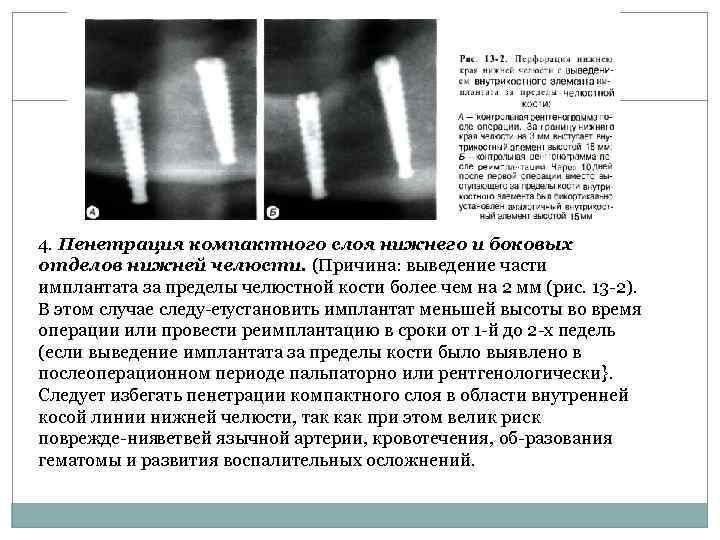

4. Пенетрация компактного слоя нижнего и боковых отделов нижней челюсти. (Причина: выведение части имплантата за пределы челюстной кости более чем на 2 мм (рис. 13 2). В этом случае следу ет установить имплантат меньшей высоты во время операции или провести реимплантацию в сроки от 1 й до 2 х педель (если выведение имплантата за пределы кости было выявлено в послеоперационном периоде пальпаторно или рентгенологически}. Следует избегать пенетрации компактного слоя в области внутренней косой линии нижней челюсти, так как при этом велик риск поврежде ния ветвей язычной артерии, кровотечения, об разования гематомы и развития воспалительных осложнений.